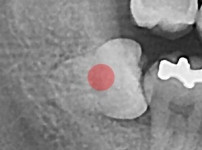

충치가 심한 사랑니